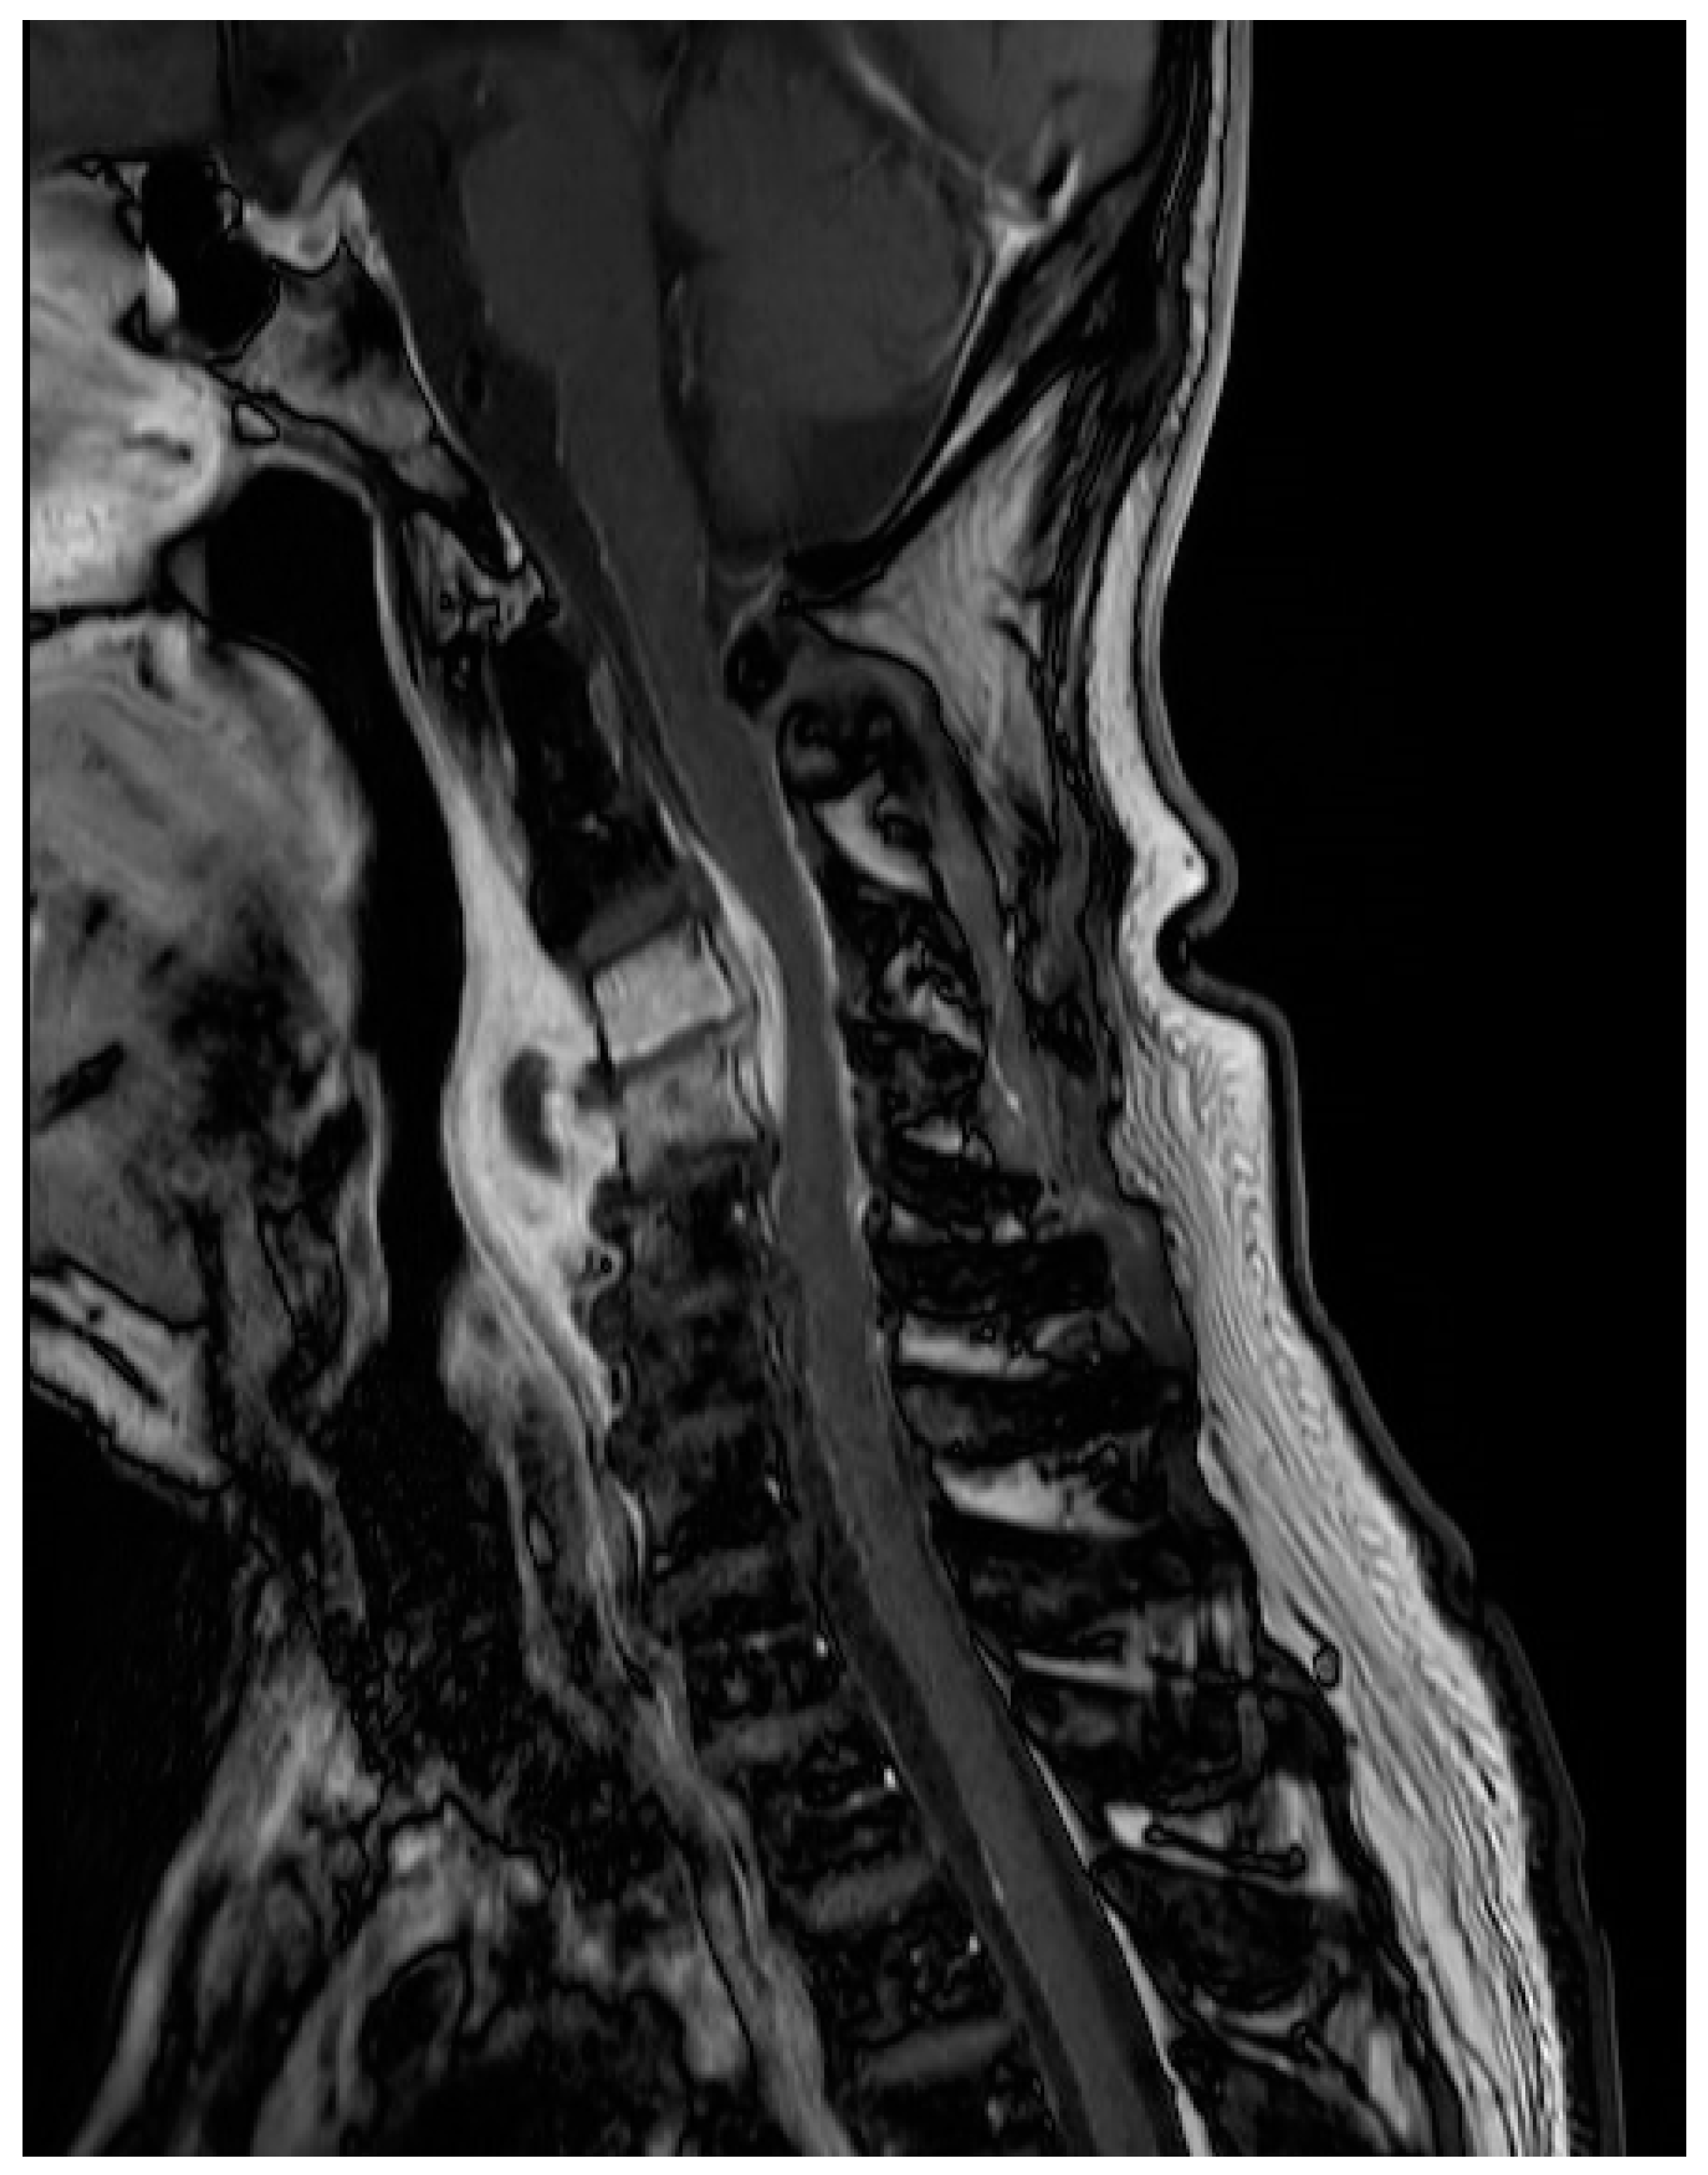

2. Case Presentation